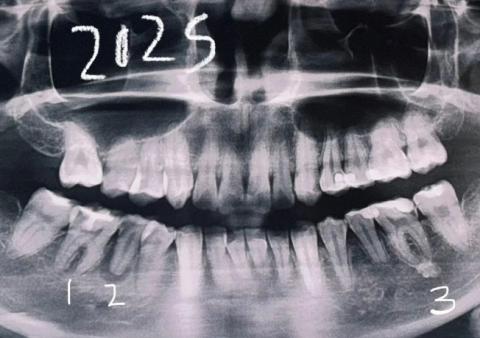

This panoramic dental X-ray shows a full-mouth view of the maxilla and mandible. Several teeth demonstrate radiographic signs of infection, bone loss, and previous dental treatment. The findings suggest chronic, multi-site dental pathology rather than a single isolated issue.

General Radiographic Findings

-

Multiple teeth with widened periodontal ligament spaces

Areas of reduced bone density around root apices

Irregular alveolar bone levels

Signs consistent with chronic inflammation

Mixed dental history including untreated, treated, and compromised teeth

Upper Jaw Findings

Possible apical radiolucencies on posterior teeth

Early to moderate bone loss

Sinus floor appears intact but close to root apices

Risk of sinus involvement if infections progress

Lower Jaw Findings

Noticeable bone loss around posterior molars

Possible chronic apical infections

Increased risk to mandibular nerve if lesions enlarge

Structural bone thinning in affected areas

Diagnosis

Chronic apical periodontitis affecting multiple teeth

Generalized dental infection with localized bone loss

Long-standing inflammatory dental condition